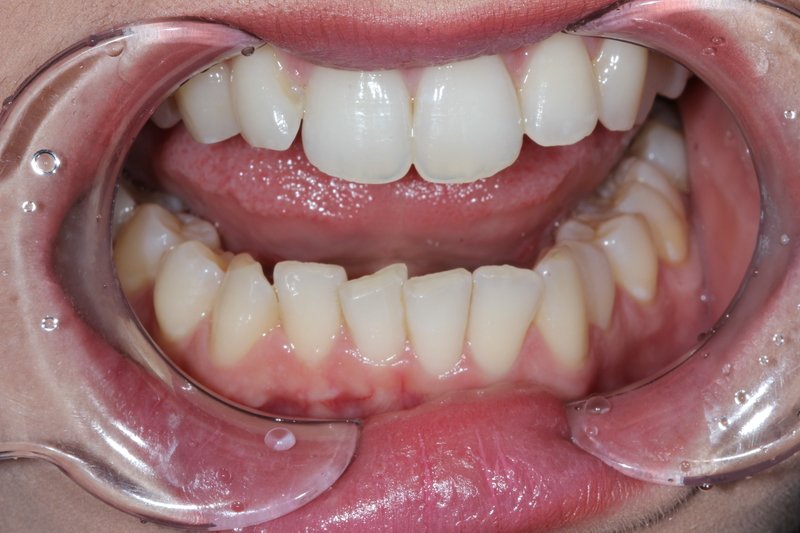

Replacement of old upper bar retained Chrome denture with fixed upper prosthesis.